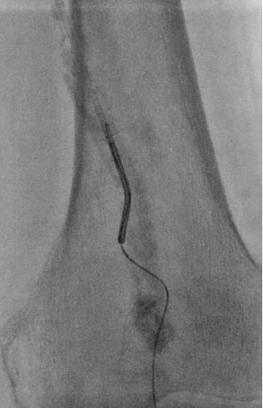

5. 选择6*60mm Shockwave冲击波球囊处理股腘动脉

本例患者股浅动脉重度闭塞,股浅远端重度钙化病变近收肌管,利用Shockwave冲击波球囊获得满意的管腔准备后联合使用DES,为保障远期通畅植入支架,支架膨胀形态理想。

我国患者股浅动脉又多以长段闭塞病变为主,为保障远期通畅率,支架的植入往往不可避免,此时如何优化支架膨胀则至关重要。利用“聚焦式”的冲击波能量作用于重度钙化环最薄弱处,在低压下安全打开钙化斑块,尤其是限制血管床弹性的环形钙化,可有效增加管腔顺应性,减少弹性回缩。